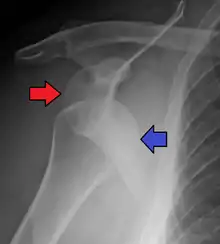

كثيراً ما يشتبه تشخيص لخلع الكتف استناداً إلى تاريخ المريض والفحص البدني. يتم إجراء الصور الشعاعية لتأكيد التشخيص. معظم الاضطرابات في مفصل الكتف تظهر في الصور الشعاعية . قد يكون من الصعب الكشف بالصور الشعاعية بأخذها من المنظر الامامى للخلع الخلفي، ولكن يمكن أخذها بسهولة في الوضعيات الأخرى. بعد رد الكتف المخلوع عادة ما تتكرر الصور الشعاعية للتأكد من النجاح في رد الكتف والكشف عن الأضرار العظمية. بعد الخلع المتكرر للكتف يمكن استخدام التصوير التصوير بالرنين المغناطيسي النووي لتقييم الضرر الأنسجة اللينة. في ما يتعلق بالخلع المتكرر للكتف، يتم اجراء اختبار مفيد في تحديد الرياضيين الذين مهيئون لخلع الكتف مستقبلا". يوجد ثلاث أنواع منه : أمامى، خافى، سفلى .

الخلع الأمامي

- يمثل 95% من خلع الكتف

- عادة تسببها ضربة مباشرة إلى الذراع أو الوقوع على ذراع في وضع مستقيم